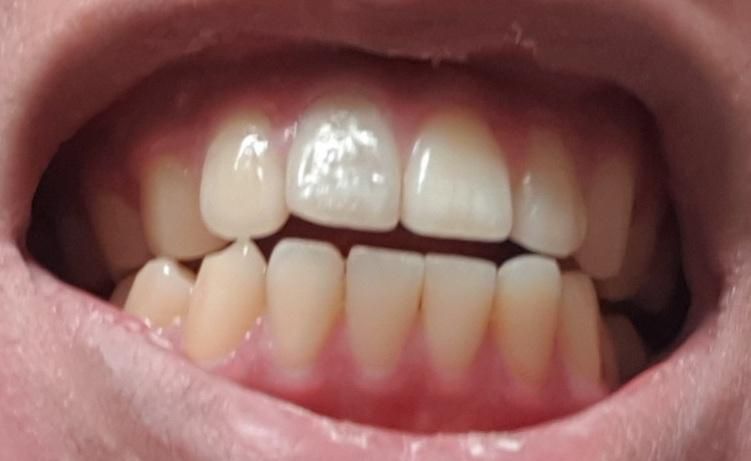

충격으로 인한 신경이 죽은 치아 수명은 어느정도 되나요?

충격으로 인해 앞니의 신경이 죽어 신경치료를 한후 크라운없이 충치도 생기지 않고 8년도넘었고 올해 9년차 동안 치아를 사용했는데 변색은 사진처럼 되어있는 상황입니다.

2.치아가 많이 누런색인거 같은데 심한편인가요?

• 2번 째 사진

2. 사진으로는 치아 색상에 대해 평가하기 어렵습니다. shade guide가 있어야 정확히 알 수 있고요. 사진상으론 그렇게 누래 보이진 않습니다.